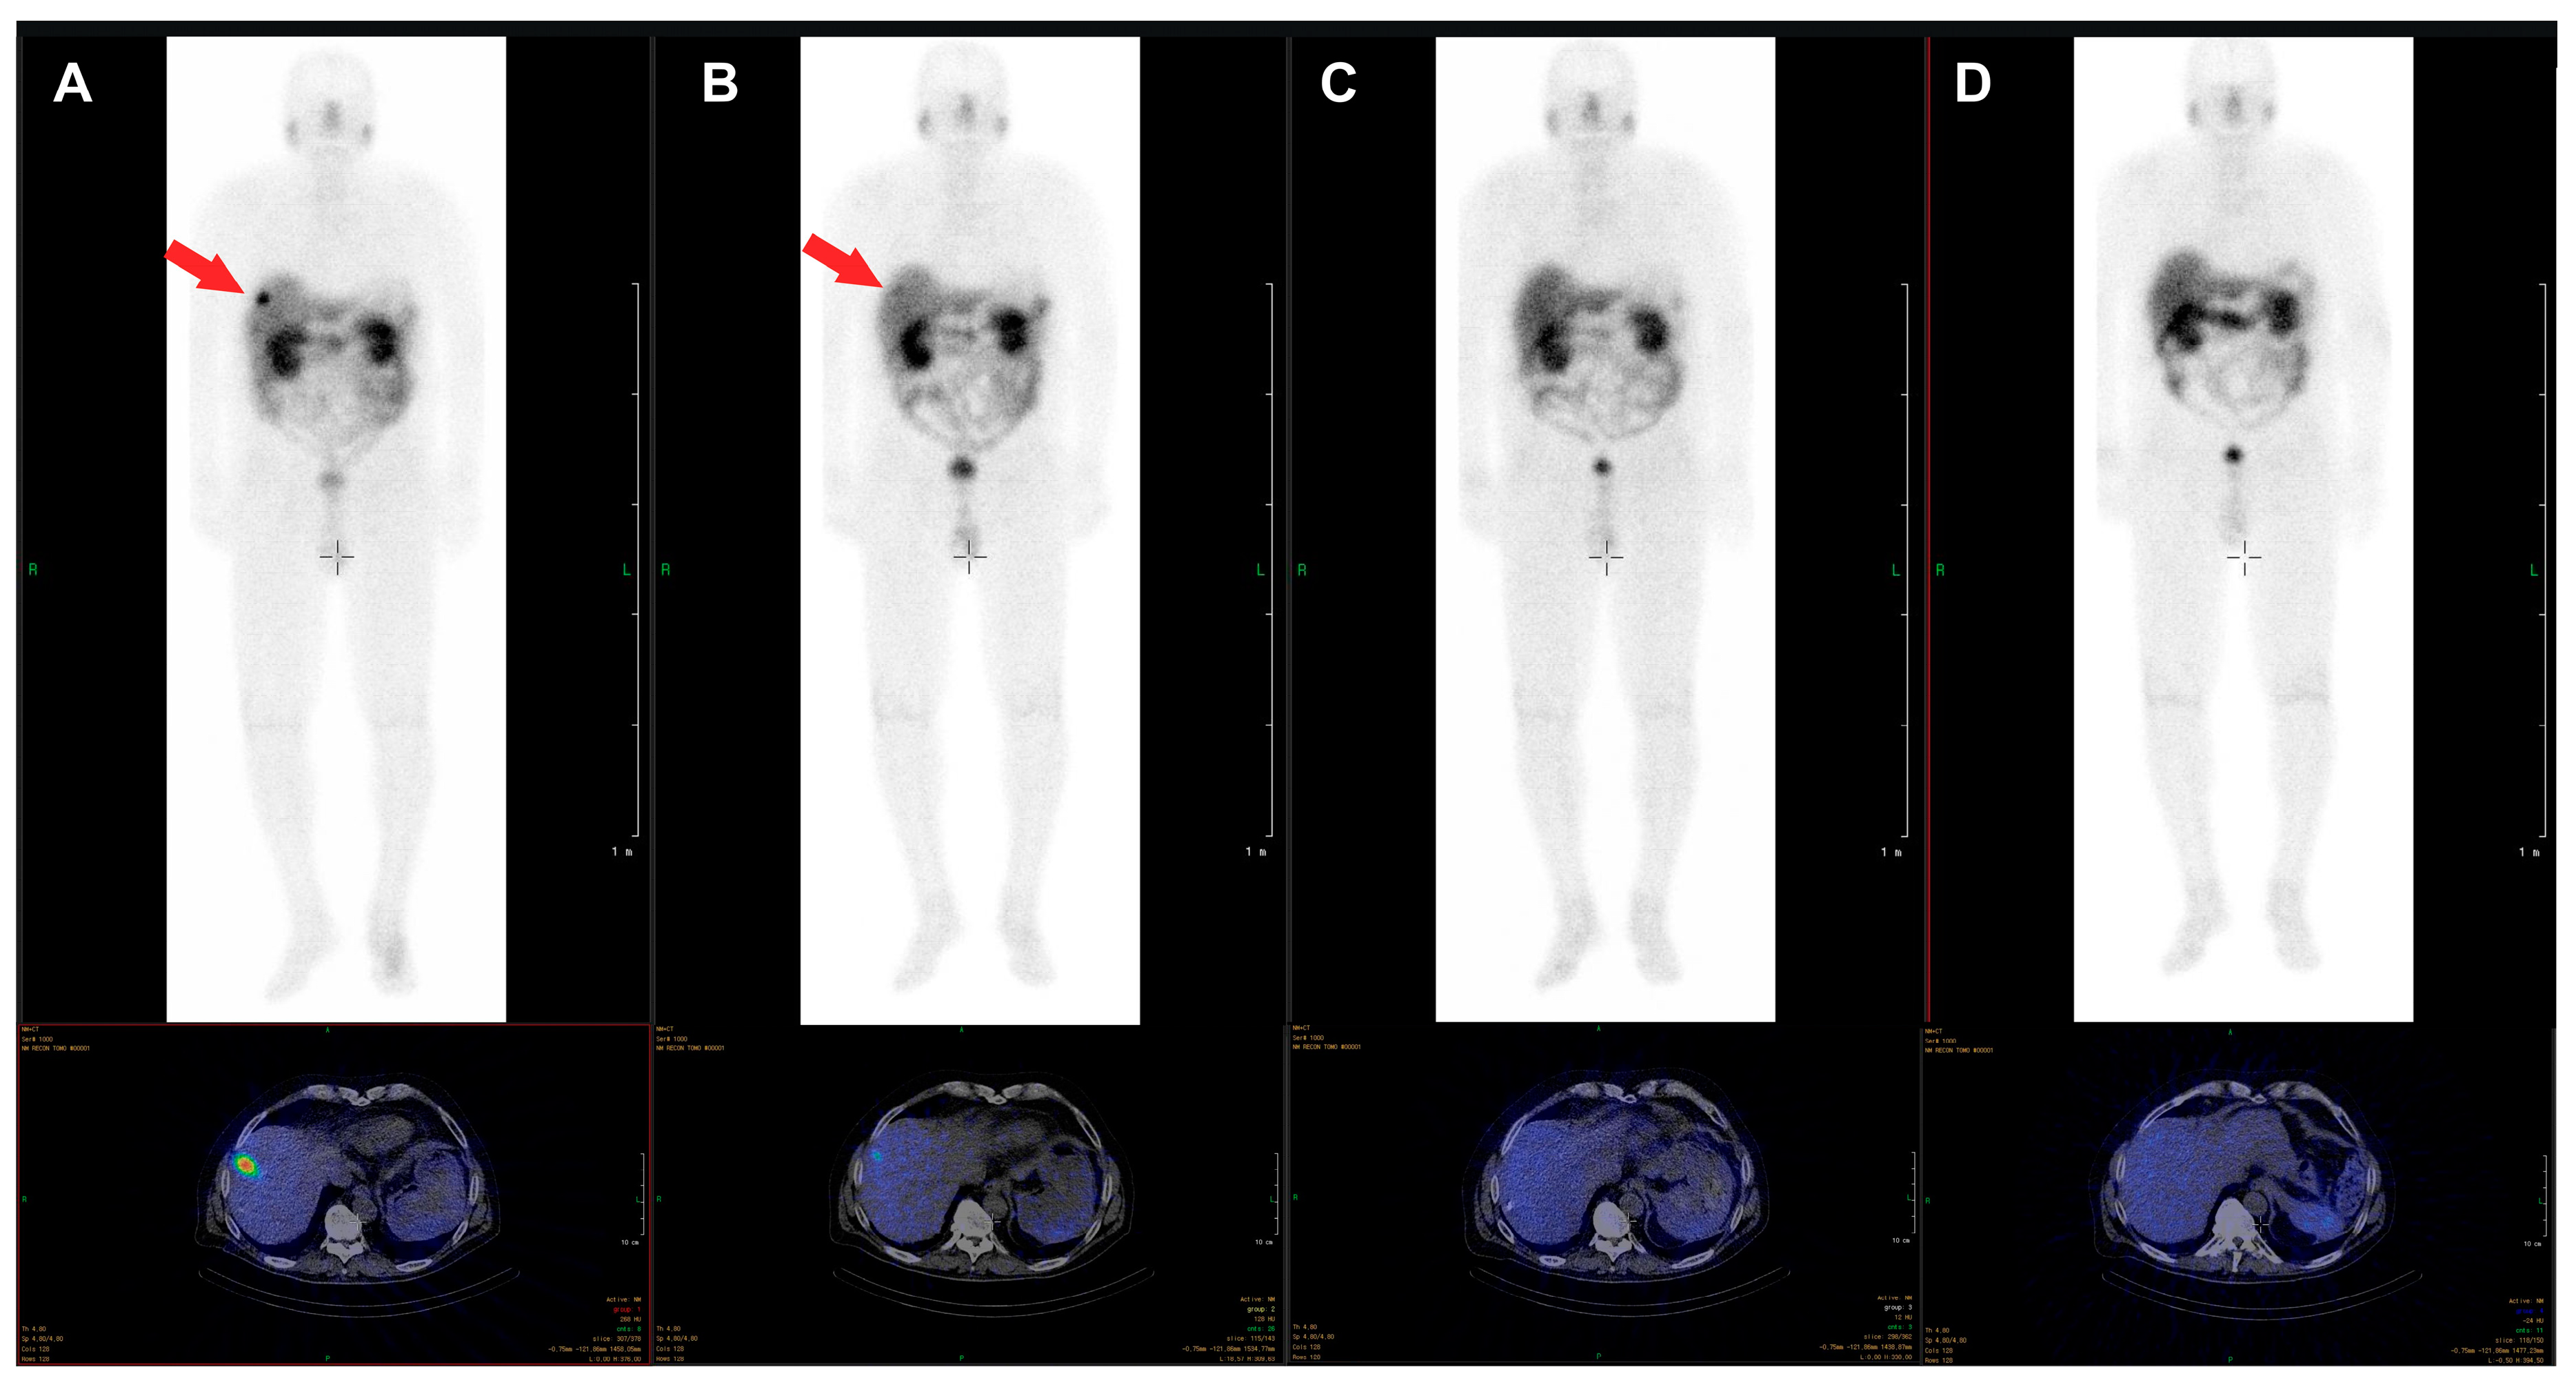

The β-emitter-labeled somatostatin analogue, 177Lu-DOTA-D-Phe-Tyr3-octreotate (DOTATATE), improves PFS, quality of live, and presumably OS. In the NETTER-1 trial, 229 patients with progressive, well-differentiated (G1 or G2) neuroendocrine tumors were randomized to be treated either with 60 mg long-acting octreotide LAR or 177Lu-DOTATATE and 30 mg octreotide LAR [20]. After 20 months, PFS was 62% in the group treated with 177Lu-DOTATATE and 30 mg Octreotide LAR compared with 11% in the Octreotide LAR group. This difference was statistically significant. The response rate was 18% in the group with radionuclide treatment vs. 3% in the group treated with Octreotide LAR. Interestingly, OS was higher in the radionuclide group too, as only 14 deaths occurred in the 177Lu-DOTATATE group compared to 26 in the Octreotide LAR monotherapy group. Radionuclide therapy did not cause increased rates of nephrotoxicity, however, the rate for grade 3 or 4 neutropenia, thrombocytopenia, and lymphopenia was 1%, 2%, and 9% respectively. Octreotide LAR (60 mg/d) monotherapy in contrast was not hematotoxic. In an additional analysis of the NETTER trial data, a higher quality of life was found in patients treated with 177Lu-DOTATATE compared to octreotide LAR monotherapy [21]. An image example of a patient with very good treatment response to 177Lu-DOTATATE is shown in Figure 1. The second example demonstrates a full response achieved with 177Lu-DOTATATE treatment. In Figure 2, images of a patient with pancreatic NETs during four cycles of treatment with a total dose of 28.8 GBq 177Lu-DOTATATE are presented. After the last cycle, no active tumor tissue was found in PET/CT imaging, and also in the follow-up after 6 and 12 months, no tumor localization could be identified, corresponding to a full response.

Figure 2. Example of a 76-year-old male patient with pancreatic NET, first diagnosed in 2012, with an initial ki-67 index of 15% who underwent four cycles of treatment with 177Lu-DOTATATE (cumulative dose 28.8 GBq) between October 2017 and July 2018, due to progression of bilobar liver metastases. The liver metastasis clearly visible in the post-therapy scan of the first cycle (A) is just barely visible in the scan of the second cycle (B) and not visible anymore in the scans of the third (C) and fourth (D) cycle. In the PET/CT images acquired six and twelve months after the last cycle, no tumor tissue was identified.